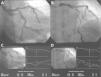

A 51-year-old man, hypercholesterolemic and an ex-smoker, was hospitalized for sudden-onset typical chest pain. The admission electrocardiogram showed slight ST-segment elevation with downward concavity in II, III and aVF (Figura 1). Urgent coronary angiography revealed a large caliber anterior descending artery, with a short proximal lesion and a long lesion in the mid segment, both with around 50% stenosis (Figura 2); there were no significant lesions in the left main, circumflex or right coronary arteries. Laboratory tests showed elevated biomarkers of myocardial necrosis (troponin 11.8μg/l, reference value <0.04μg/l). The echocardiogram showed good global and segmental left ventricular function. Stress cardiac magnetic resonance imaging (MRI) was requested, with a view to aiding differential diagnosis between myocardial infarction with spontaneous reperfusion and myopericarditis, as well as to assess the ischemic repercussions of the lesions in the anterior descending artery. This was performed on the sixth day of hospital stay, and showed focal subepicardial delayed enhancement at the transition between the mid and apical inferior segments, with a slightly increased T2 signal suggestive of edema at this point (Figura 3), and normal perfusion during the first pass of paramagnetic contrast under adenosine stress and at rest (Figura 4). A diagnosis of myocarditis was therefore made, given the absence of stress-induced ischemia. The lack of subendocardial delayed enhancement meant that infarction with spontaneous reperfusion could be definitively excluded. The patient was discharged one week after the acute event and has since remained asymptomatic.